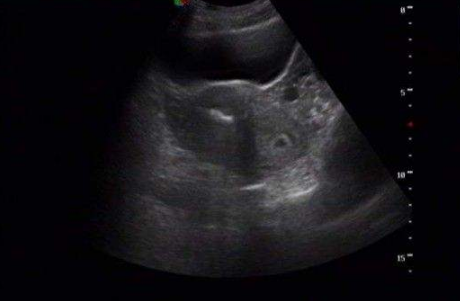

雙角子宮圖片

雙角子宮 (55)